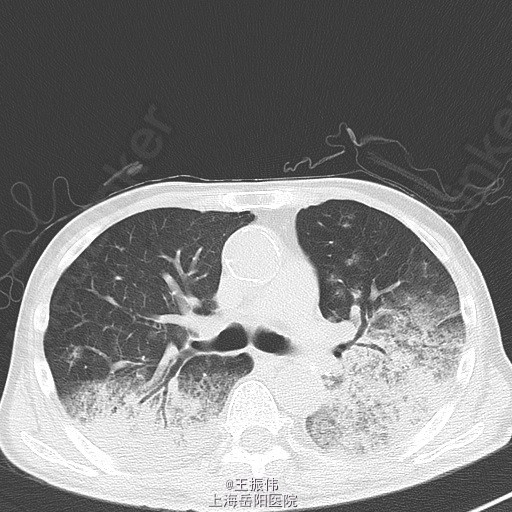

气管居中,颈静脉正常,胸廓两侧对称,无桶状胸,呼吸运动两侧对称,呼吸频率24次/分,肋间隙正常,无胸膜摩擦感。两肺叩诊可及清音,两肺有湿性啰音,(7.17 岳阳医院)CRP:24.09mg/L,血常规:WBC8.4*10^9/L,N77%。(7.19)[胸部CT,平扫](21516866)1.结合病史,左肺术后;两肺炎症,请治疗后复查。2.右侧胸腔积液,双侧胸膜增厚。3.主动脉及冠脉血管壁钙化。4.甲状腺右叶低密度影,请进一步检查。请结合增强检查。癌胚抗原CEA:27.97;糖类抗原CA199:大于 700;细胞角蛋白19片段(CYFRA21-1):8.6630;糖类抗原CA-50:大于500;糖类抗原CA242:大于200;SCC鳞癌相关抗原:4.629ng/ml